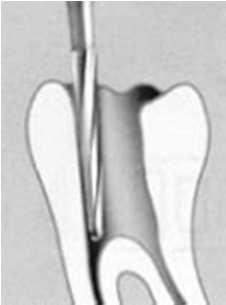

Algunos autores consideran  a la conformación de la entrada de los conductos, como parte de la rectificación de la cámara pulpar. Ver imagen derecha Superior.

• A: Apertura,

• B,C y D: Rectificación de las paredes de la cámara pulpar.

• E: Conformación del acceso a los conductos en el tercio coronal con fresas de Gates Glidden.

El resultado final debe ser una cavidad de acceso que permita a los instrumentos endodóncicos alcanzar los orificios de entrada de los conductos sin interferencia alguna y lo más rectilíneamente posible. Ver imágenes derecha.